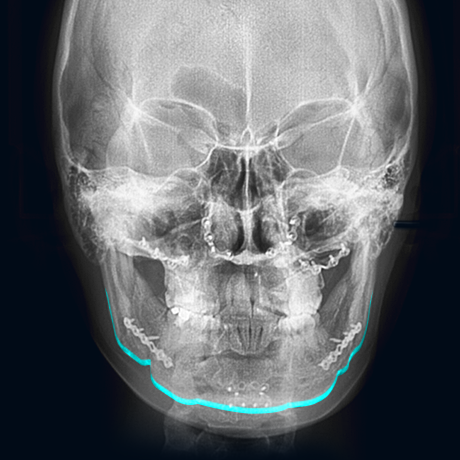

V라인 사각턱 재수술로

뭉툭한 앞턱을 개선하고

울퉁불퉁한 라인을

매끄럽게 정리하여 완성